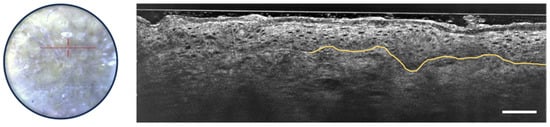

LC-OCT has shown promise in diagnosing and distinguishing squamous cell carcinoma and actinic keratosis. Several studies [37,38] have identified LC-OCT criteria for AK, including hyperkeratosis (irregular, hyper-reflective stratum corneum), cellular and nuclear pleomorphism affecting basal and upper epidermal layers and a well-defined DEJ along the entire lesion as can be seen in Figure 8. The ability of LC-OCT to visualize the basal growth pattern of AK enables non-invasive classification based on the histological PRO classification. Comparing AK and SCC, both exhibit cytological and architectural alterations, such as epidermal pleomorphism, cellular atypia, and dilated and glomerular vessels [39,40]. Nevertheless, AK is associated with a preserved DEJ, whereas SCC shows a non-visible or interrupted DEJ [40]. LC-OCT outperformed RCM in visualizing key features of keratinocyte skin tumors, including parakeratosis, dyskeratotic keratinocytes, and dilated and glomerular vessels [41]. Overall, LC-OCT holds significant potential for the real-time, non-invasive diagnosis and subtyping of AK and SCC and its advantages over RCM highlight its clinical utility.

Figure 8.

Dermoscopic image (left) and vertical sectional LC-OCT image (right) of an actinic keratosis (AK). Unusual organization, size and shape of keratinocyte nuclei within the epidermis, hyperkeratosis, undulated but still defined DEJ, partially drawn in yellow. The red horizontal line superimposed on the dermoscopic image delineates the location of the vertical sectional LC-OCT image. Scale bar: 100 µm.